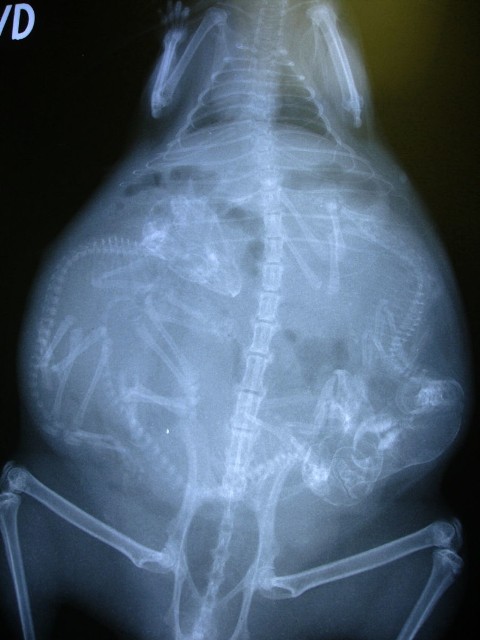

Մենք բոլորս լավ պատկերացնում ենք, թե ինչպես է անցնում մարդու հղիությունը, և շնորհիվ ժամանակակից տեխնոլոգիաների՝ կարող ենք տեսնել երեխային մայրիկի արգանդում հղիության ամենավաղ փուլում։ Իսկ ինչպե՞ս է ընթանում կենդանիների հղիությունը։ Մասնագետները, ովքեր հոգ են տանում հղի կենդանիների մասին, ներկայացրել են նրանց ռենտգենային և ուլտրաձայնային լուսանկարները, որոնք ձեր դատին է հանձնում «twizz.ru» կայքը։

Կատու